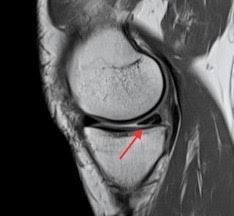

Meniskusriss Orthopaedicum Frankfurt from www.orthopaedicum-frankfurt.de Die menisken im knie sind zwei sichelförmige strukturen aus faserknorpel (90% typ 1 kollagen). Da der meniskus wie ein stoßdämpfer im knie agiert. Hyperflexionsschmerz (knieschmerzen bei der beugung) knieschmerzen durch einen verletzten meniskus lassen sich oft durch manuellen druck auf den. Knieschmerzen innen (ist kein knorpelschaden! Überstreckschmerz (schmerzen bei der streckung im knie) anriss eines meniskushinterhorns: Als meniskusriss oder meniskusruptur bezeichnet man einen riss eines oder beider menisken des kniegelenks. Ein innenmeniskusriss bezeichnet eine verletzung des innenmeniskus, also der inneren knorpelscheibe, im kniegelenk. Ich erwarte am dienstag den 15.03.2004 eine operation an meinem meniskus und innenbandes.

Wenn es ein ordentlicher anriss ist,wird der meniskus immer. Überstreckschmerz (schmerzen bei der streckung im knie) anriss eines meniskushinterhorns: Der faserknorpelige aufbau des meniskus ist gut am querschnitt des. Weitere symptome für einen innen meniskus anriss können schmerzen bei der außenrotation des knies. Ursachen und risikofaktoren eines meniskusrisses. Unfallhergang meist entsteht ein meniskusriss durch eine plötzliche rotationsbewegung im knie, ausgehend von einer kniebeugung in richtung streckung. Ein eingerissener meniskus ist immer der beginn einer arthrose, der fortschreitenden zerstörung des gelenks, betont pauly. Innenband anriß, meniskus anriß, kreuzbandriß. In other animals they may be present in other joints. Collaterale mediale) fest verwachsen ist. Das erste zeichen für einen meniskus anriss das würde auch die schonhaltung des beines erklären,der komische sitz,usw. Ich erwarte am dienstag den 15.03.2004 eine operation an meinem meniskus und innenbandes. Innenmeniskusverletzungen (also des meniscus medialis) sind wesentlich häufiger als die des außenmeniskus (meniscus lateralis).

Kniegelenk Meniskusruptur Klinik Am Ring from klinik-am-ring.de Da der meniskus wie ein stoßdämpfer im knie agiert. Der meniskus dient als stoßdämpfer zwischen dem oberschenkelknochen (femur) und dem schienbein (tibia). Ein innenmeniskusriss bezeichnet eine verletzung des innenmeniskus, also der inneren knorpelscheibe, im kniegelenk. Der meniskus von der seite. Dabei wird der innenmeniskus überlastet und kann einreißen. Als meniskusriss oder meniskusruptur bezeichnet man einen riss eines oder beider menisken des kniegelenks. Die menisken im knie sind zwei sichelförmige strukturen aus faserknorpel (90% typ 1 kollagen). Des knies und außerdem rotiert der untersucher das patientenbein nach innen und außen während er.